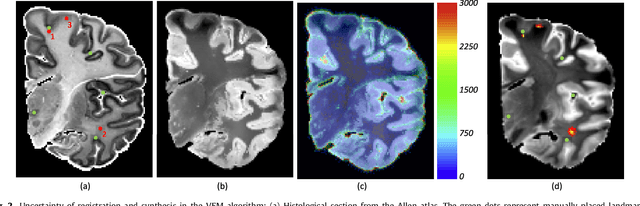

Nonlinear registration of 2D histological sections with corresponding slices of MRI data is a critical step of 3D histology reconstruction. This task is difficult due to the large differences in image contrast and resolution, as well as the complex nonrigid distortions produced when sectioning the sample and mounting it on the glass slide. It has been shown in brain MRI registration that better spatial alignment across modalities can be obtained by synthesizing one modality from the other and then using intra-modality registration metrics, rather than by using mutual information (MI) as metric. However, such an approach typically requires a database of aligned images from the two modalities, which is very difficult to obtain for histology/MRI. Here, we overcome this limitation with a probabilistic method that simultaneously solves for registration and synthesis directly on the target images, without any training data. In our model, the MRI slice is assumed to be a contrast-warped, spatially deformed version of the histological section. We use approximate Bayesian inference to iteratively refine the probabilistic estimate of the synthesis and the registration, while accounting for each other's uncertainty. Moreover, manually placed landmarks can be seamlessly integrated in the framework for increased performance. Experiments on a synthetic dataset show that, compared with MI, the proposed method makes it possible to use a much more flexible deformation model in the registration to improve its accuracy, without compromising robustness. Moreover, our framework also exploits information in manually placed landmarks more efficiently than MI, since landmarks inform both synthesis and registration - as opposed to registration alone. Finally, we show qualitative results on the public Allen atlas, in which the proposed method provides a clear improvement over MI based registration.